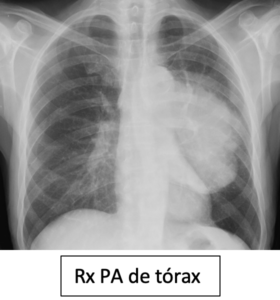

HALLAZGOS RADIOLÓGICOS

Opacidad pulmonar izquierda (anterior), bien definida.

Opacidad pulmonar izquierda (posterior), bien definida.

Opacidad pulmonar izquierda anterior, mal definida.

Opacidad pulmonar izquierda posterior, mal definida.